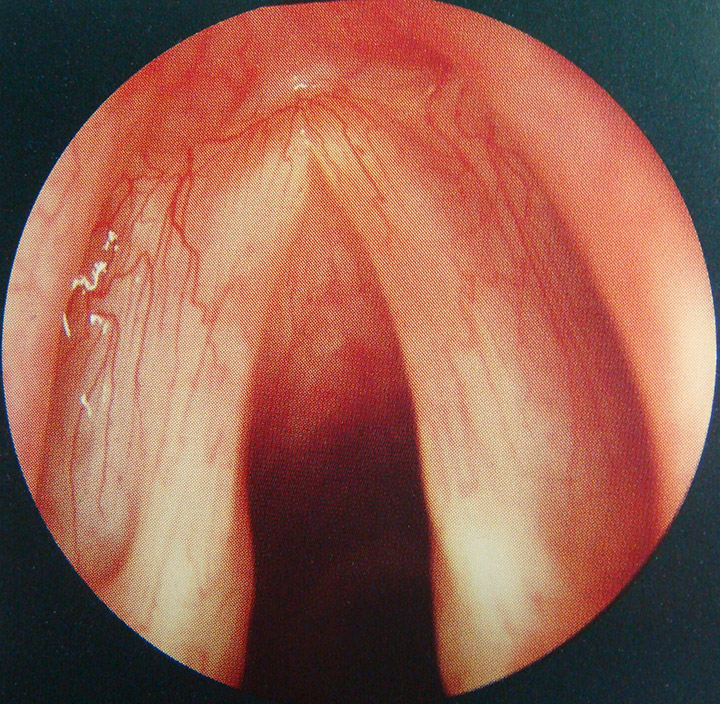

להלן מספר תמונות הממחישות את מיתרי הקול התקינים, ודוגמאות לבעיות שפוגעות במיתרי הקול כגון יבלות, ציסטה ופוליפים.